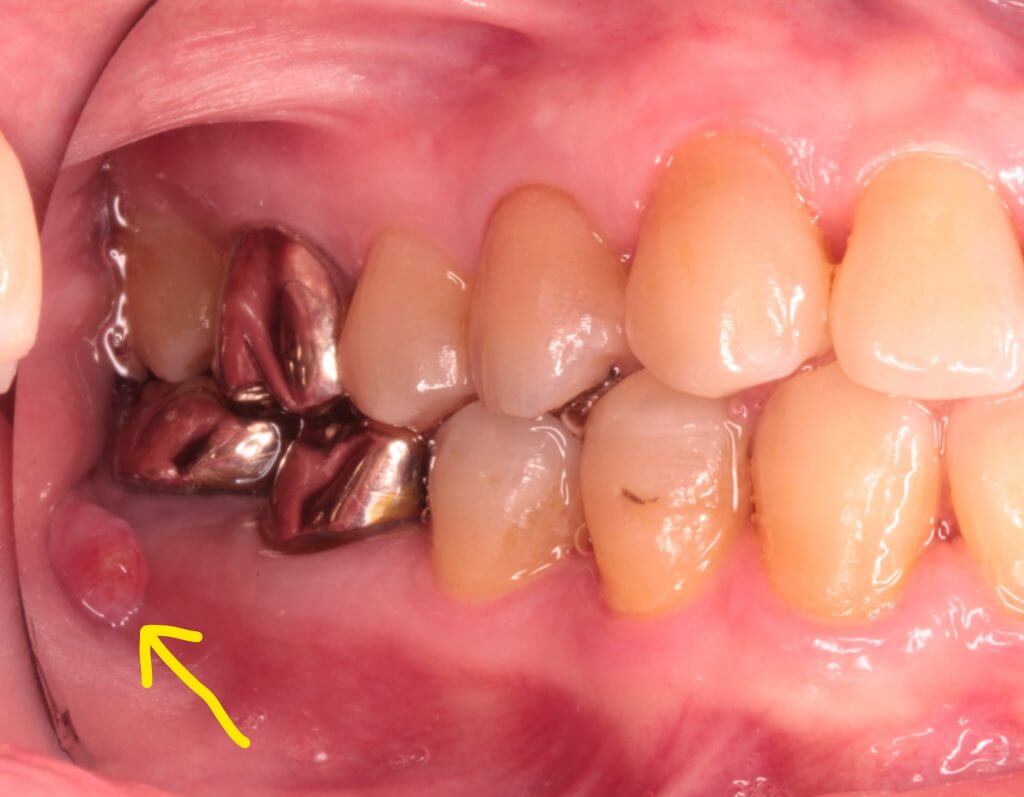

右下の奥歯のぷくっとした腫れが中々治らないという患者さんです。

デンタル撮影でも根尖部に透過像があります。

フィステルは一度は小さくなったのですがやはり完治しないので患者さんと相談の上

意図的再植術を行うこととしました。